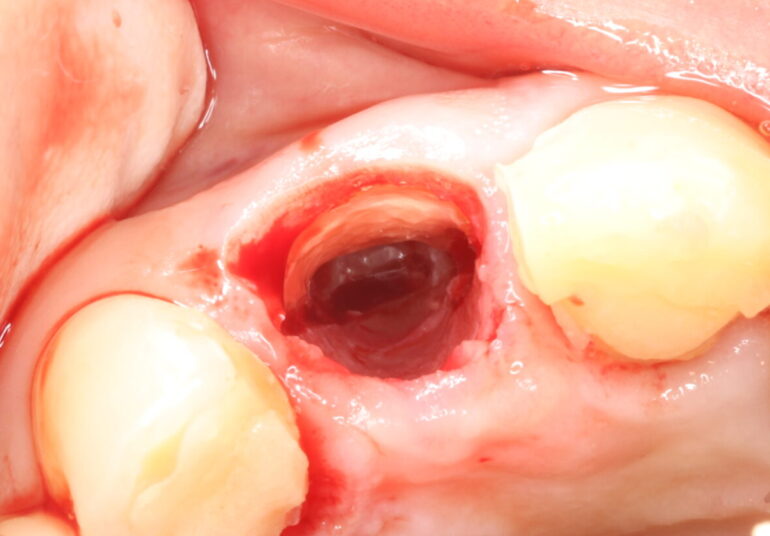

術中の写真を見てみましょう。

写真の向きとして上が唇側です。抜歯した穴に歯の一部が残っているのがわかるでしょうか。

綺麗に分割できています。この後、人工骨を歯を抜いた穴に入れて、インプラントを埋入しました。